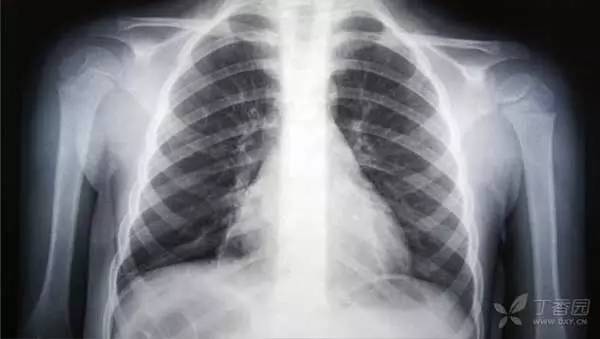

7.肺炎(由肺结核以及性传播疾病引起除外):106 亿美元

许多患者其实无需住院治疗。